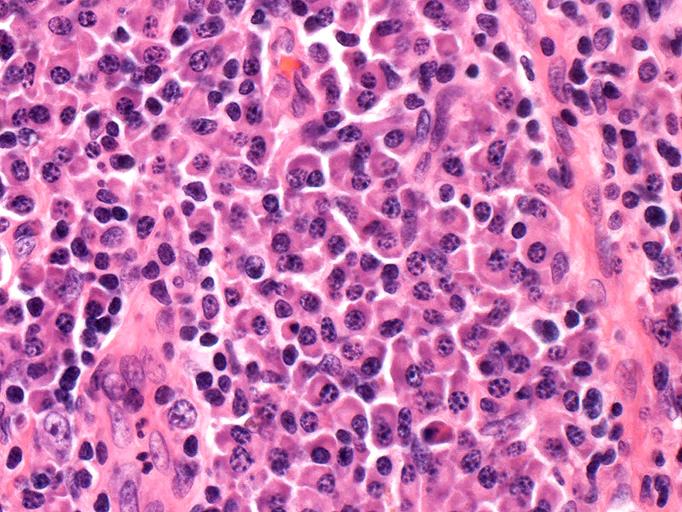

形質細胞型 plasma cell type

- 肉眼所見では3-15cmで数個の独立した結節からなる病変。小さな周囲リンパ節を伴うこともある。

- HV型と異なり種々の症状や異常検査値を示す

これらの異常は胚中心細胞の産生するIL-6のためと考えられている。患者さんの血清IL-6は高値のことが多く, 抗IL-6抗体が検出の報告もある。

2. 形質細胞型 plasma cell type(PC型):増加を示す濾胞間にびまん性密に多クローン性形質細胞浸潤が認められる。